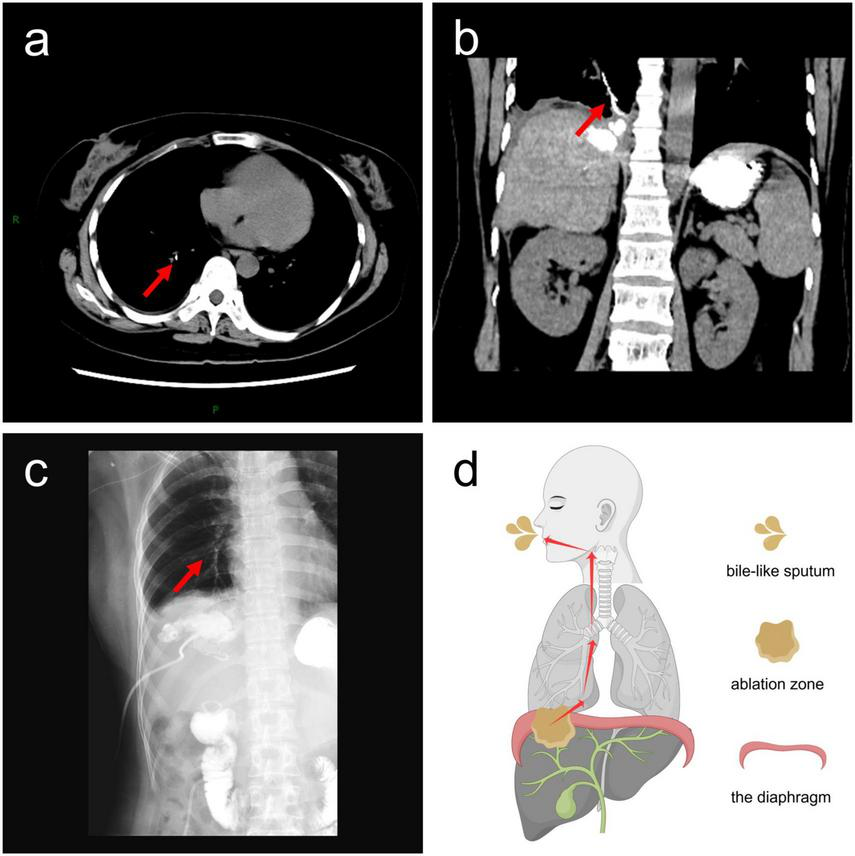

FIGURE 2

Imaging findings of bronchobiliary fistula (BBF). (a) Axial computed tomography (CT) image showing contrast agent within the fistula tract; (b) coronal CT image showing contrast agent within the fistula tract; (c) plain radiograph showing contrast agent within the fistula tract. The contrast agent within the fistula tract is indicated by red arrows; (d) the diagram illustrates the process by which bile passes through the diaphragm into the right segmental bronchus and is ultimately coughed out via the main bronchus and oral cavity. The red arrows indicate the direction of bile flow.

A 35-years-old female patient with liver metastases from colon cancer underwent PMWA on August 5, 2022, targeting a lesion in the right hepatic lobe adjacent to the diaphragm (Figures 1a, b). She had no history of chronic obstructive pulmonary disease (COPD), subphrenic bullae, tuberculosis, or bronchiectasis. She developed fever with a maximum temperature of 39 °C on August 6, 2022, and blood cultures revealed Klebsiella oxytoca. Contrast-enhanced computed tomography (CT) on August 10, 2022, revealed the formation of a pyogenic liver abscess (PLA) (Figure 1c). Percutaneous drainage of the abscess was performed on August 16, 2022 (Figure 1d). Following antibiotic therapy and drainage, her fever subsided after September 21, 2022. However, she subsequently presented with typical bilioptysis, which was highly suggestive of BBF. To confirm the diagnosis, contrast agent was injected via the drainage tube followed immediately by CT and plain radiography on September 22, 2022. The imaging findings (Figures 2a–d), especially the coronal CT image (Figures 2b, d), clearly demonstrated extravasation of contrast agent from an intrahepatic bile duct branch, forming an abnormal fistula tract through the diaphragm and directly entering the right lower lobe bronchial tree. This imaging evidence was fully consistent with the patient’s clinical symptoms. According to the literature, direct visualization of the fistula tract on cholangiography is a reliable method for the diagnosis of BBF, and detection of bilirubin in sputum can also serve as supporting evidence (9). Therefore, this case was diagnosed as acquired BBF. Despite 13 days of adequate drainage and antibiotic therapy, the patient continued to cough up bile-like sputum. Therefore, on October 4, 2022, PMWA at an ablation watt of 40 w was performed on the fistula tract for 7 min to achieve closure (Figure 3a). A post-ablation CT scan confirmed closure of the fistula tract (Figures 3b, c). A follow-up CT scan on October 12, 2022, again demonstrated closure of the fistula (Figure 3d), and the patient no longer coughed up bile-like sputum.